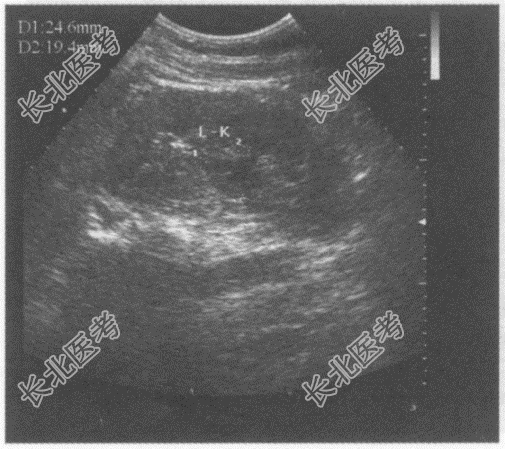

- 单项选择题临床资料:男, 48岁,常规体检。

超声综合描述: 左肾集合系统中部可见2.5cm×1.9cm低回声区,形态不规则, CDFI:内见少许动、静脉血流信号。见下图及彩图。

超声提示:  A、左肾肥大肾柱

B、左肾盂旁囊肿

C、左肾积水

D、左肾集合系统中部实性占位

E、右肾错构瘤